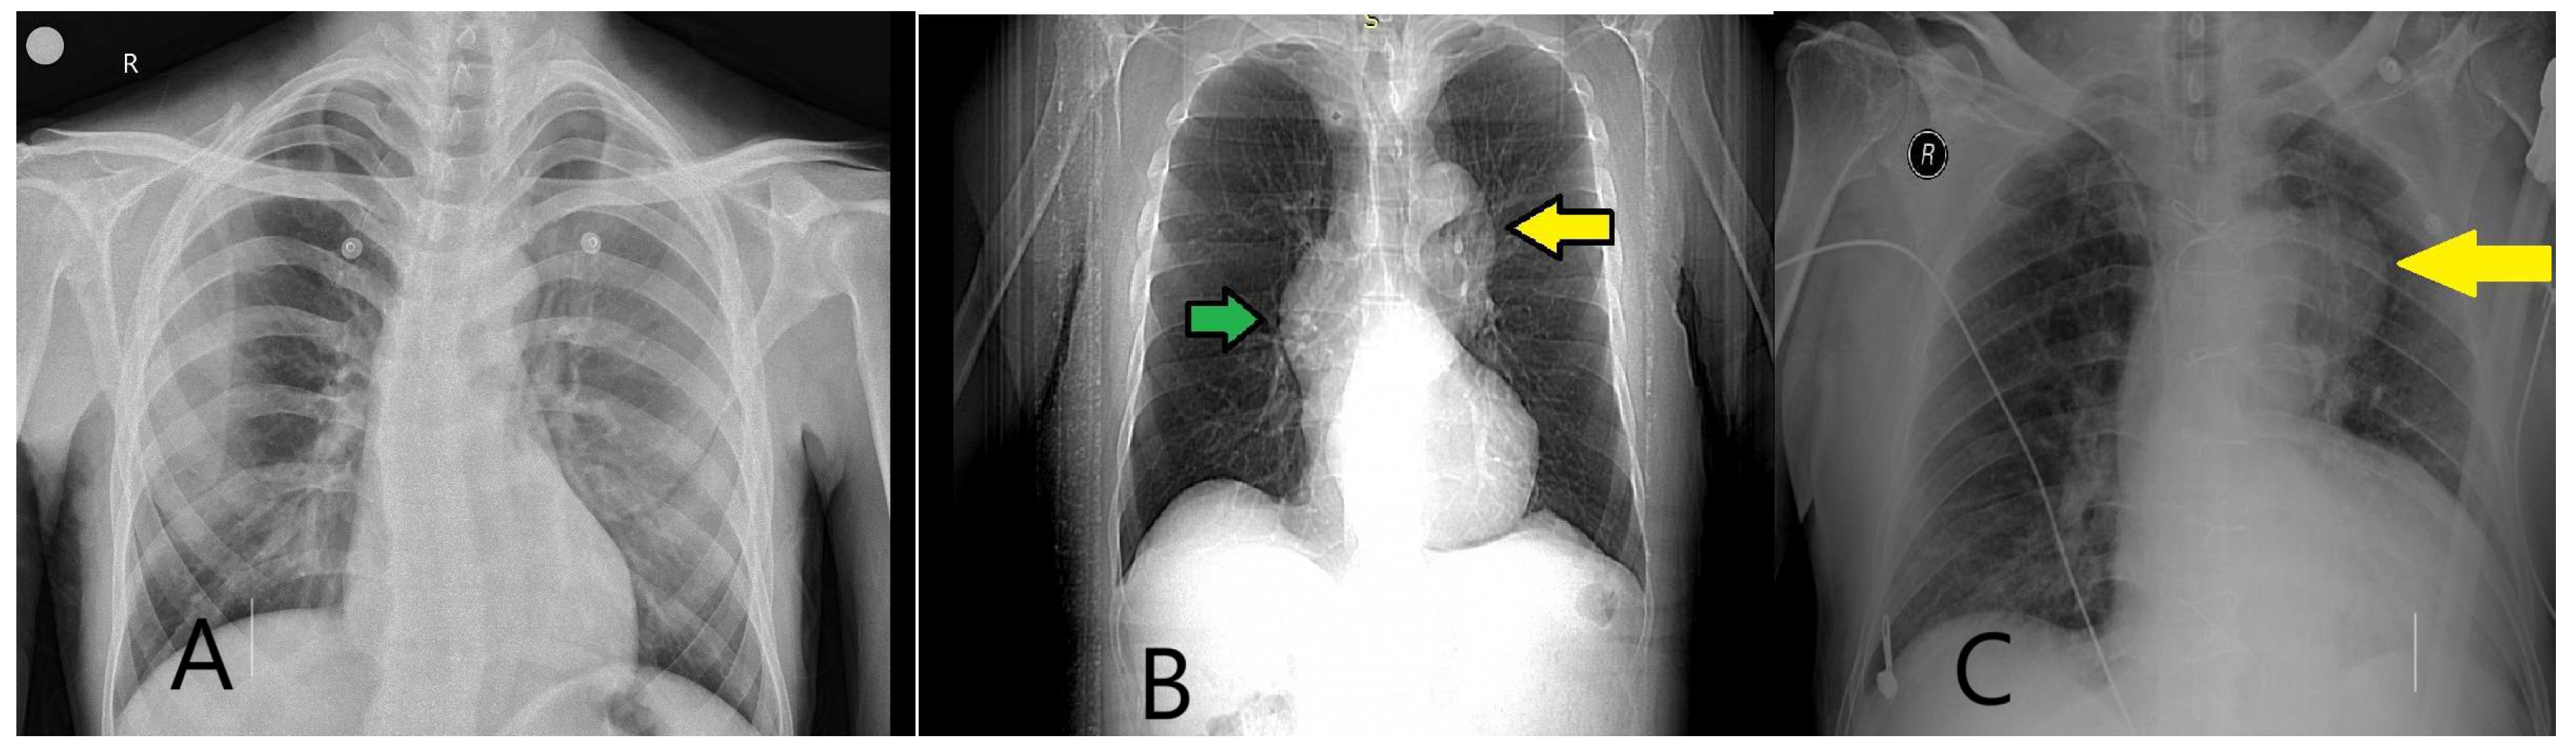

- Song, D.H.; Choi, J.H.; Lee, J.Y. Predicting acute aortic syndrome using aortic dissection detection risk score, D-dimer, and X-ray. Heliyon 2023, 9, e20578. [Google Scholar] [CrossRef]

- Morello, F.; Santoro, M.; Fargion, A.T.; Grifoni, S.; Nazerian, P. Diagnosis and management of acute aortic syndromes in the emergency department. Intern. Emerg. Med. 2021, 16, 171–181. [Google Scholar] [CrossRef] [PubMed]

- Nazerian, P.; Pivetta, E.; Veglia, S.; Cavigli, E.; Mueller, C.; de Matos Soeiro, A.; Leidel, B.A.; Lupia, E.; Rutigliano, C.; Wussler, D.; et al. ADvISED Investigators. Integrated Use of Conventional Chest Radiography Cannot Rule Out Acute Aortic Syndromes in Emergency Department Patients at Low Clinical Probability. Acad. Emerg. Med. 2019, 26, 1255–1265. [Google Scholar] [CrossRef] [PubMed]